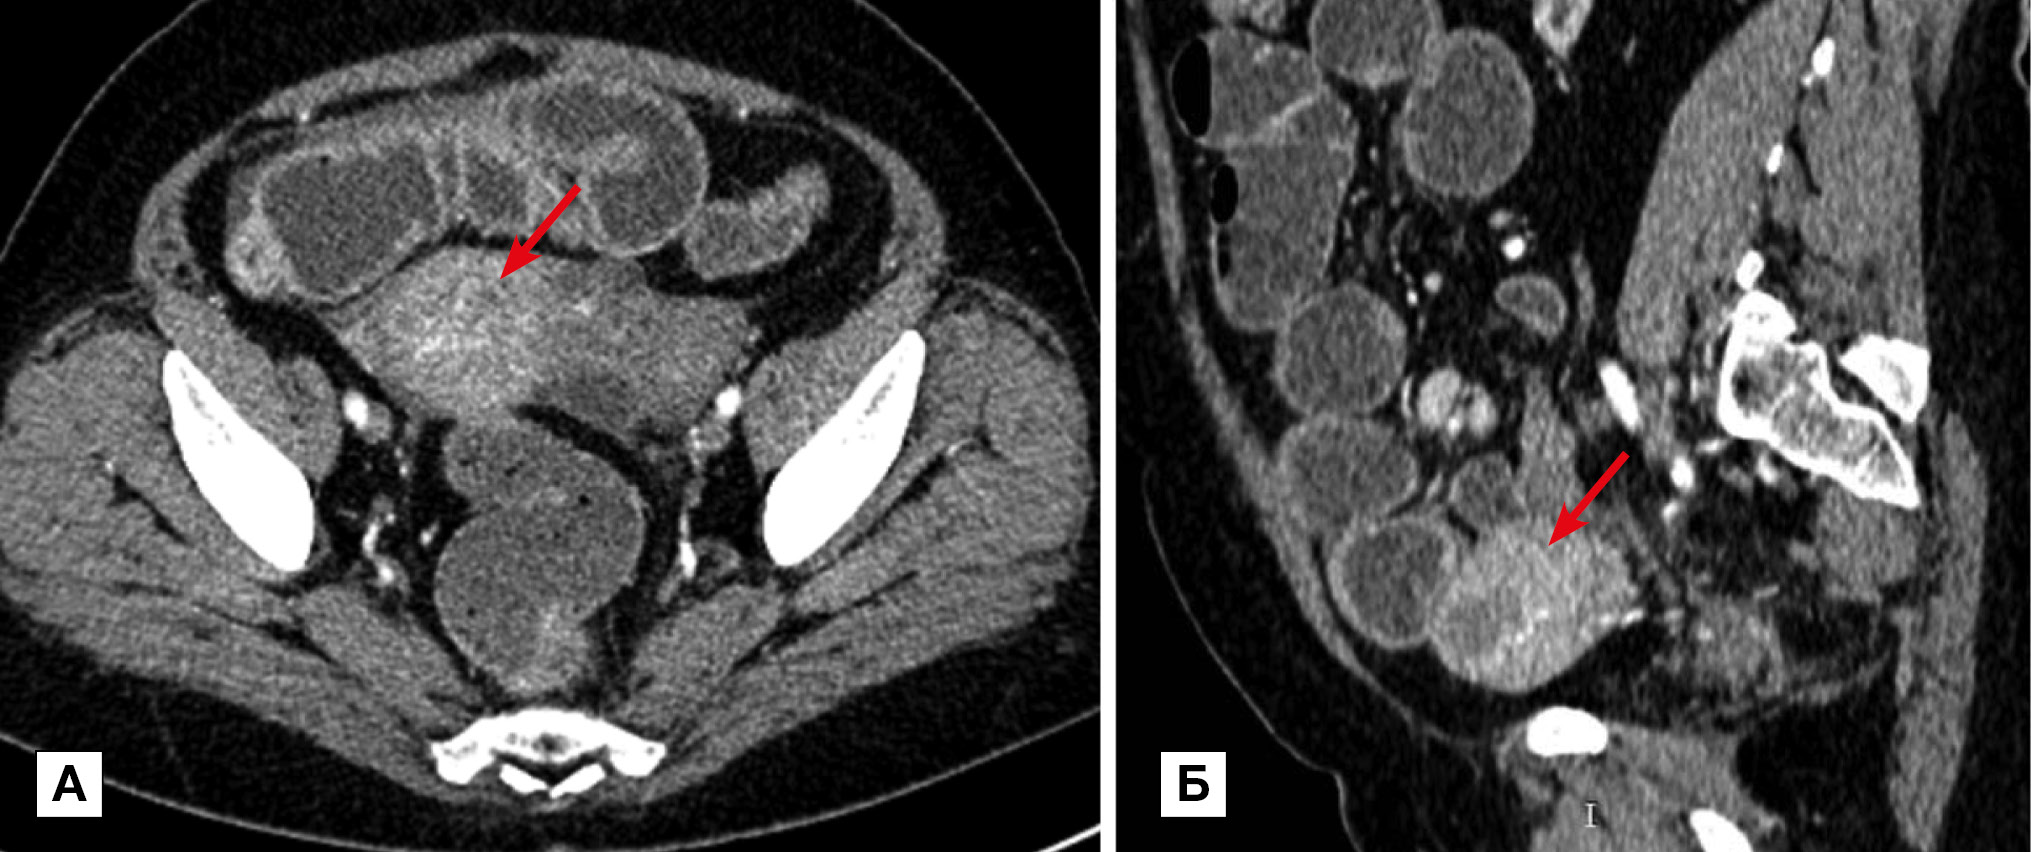

Рис. 4. Больная, 36 лет. МСКТ: В-клеточная лимфома, инфильтративная форма

Примечание. В 4-й части двенадцатиперстной и проксимальном отделе тощей кишок определяется утолщение стенки до 40 мм и неравномерное расширение просвета за счет разрастания опухолевой ткани (прямые стрелки). Опухолевые разрастания имеют равномерную солидную структуру, которая при внутривенном контрастировании однородно накапливает контрастный препарат. По интенсивности накопления ткань опухоли изоденсивна с неизмененной стенкой кишки. Лимфатические узлы брыжейки и забрюшинного пространства увеличены (изогнутые стрелки).

Реже лимфома проявлялась солидными эксцентрическими узловыми или полиповидными разрастаниями (узловая и полиповидная формы соответственно). Эти формы (4 наблюдения, 25%) отличались от «классического», описанного выше варианта лимфомы. В этих случаях столь выраженного утолщения стенки не определялось. Изменения стенки сопровождались нехарактерным сужением просвета. По этому признаку узловая форма имела общие черты с раковой опухолью, а полиповидная форма — с раком и болезнью Крона. На рис. 5 представлено наблюдение больного узловой формой В-клеточной лимфомы. В представленном наблюдении узловые разрастания уменьшали просвет кишки; протяженность поражения составляла 100–150 мм. В «переходной» зоне определялось минимальное престенотическое расширение, что напоминало картину экзофитной формы аденокарциномы. Полиповидная форма лимфомы по характеру утолщения и протяженности поражения стенки ТК имела картину, возможную при раковой опухоли или болезни Крона. Утолщение стенки при этой форме обычно не превышало 10 мм, протяженность — от 50 до 100 мм.

Рис. 5. Больной, 46 лет. МСКТ: В-клеточная лимфома тощей кишки, узловая форма. Анемия

Примечание. А — исследование с контрастированием просвета кишки per os. Б — артериальная фаза контрастного усиления: в стенке тощей кишки определяются мягкотканные узловые разрастания, суживающие и деформирующие просвет кишки; признаков кишечной непроходимости нет. Уплотнение прилежащего отдела брыжейки без признаков десмопластической реакции (стрелка). В брыжейке — увеличенные лимфатические узлы (пунктирная стрелка).

Контрастирование внутреннего просвета кишки per os позволяло визуализировать относительно крупные полипы, которые отображались характерными дефектами наполнения по контуру (рис. 6). Мелкие полипы трудно визуализировались на КТ даже в условиях заполненного водой внутреннего просвета. В одном из двух наблюдений полиповидной формы лимфомы сужение просвета кишки вызвало обтурационную непроходимость. Из других осложнений мы диагностировали формирование абсцесса на брыжейке пораженной кишки больного узловой формой лимфомы, при которой изъязвления в стенке привели к пенетрации и прободению. На КТ определялась типичная картина осумкованного скопления жидкости, одну из стенок которого представляла тонкая кишка.

Рис. 6. Больной, 51 год. МСКТ: В-клеточная лимфома, полиповидная форма. Контрастирование просвета кишки per os

Примечание. Определяется утолщение стенки терминального отдела подвздошной кишки. По контуру контрастированного просвета хорошо заметны полиповидные разрастания (стрелка). Обнаруживается распространение поражения на брыжейку (пунктирная стрелка) и значительное увеличение регионарных и забрюшинных лимфатических узлов (области обозначены овалом).

Мезентериальная, первично множественная форма лимфомы (5 наблюдений) проявлялась КТ-картиной распространенного поражения лимфатических узлов. В наших наблюдениях лимфом желудка, ТК, толстой кишки в различных сочетаниях встречались неоднократно и сопровождались распространенным увеличением лимфатических узлов. Пораженные участки кишки располагались на отдаленных друг от друга участках. На рис. 7 представлено наблюдение первично-множественной лимфомы у пациентки 68 лет. В течение последнего года больная предъявляла жалобы на общую слабость, потливость, повышение температуры тела, периодические ноющие боли в животе, снижение массы тела. На компьютерных томограммах выявлена первично-множественная лимфома с поражением желудка и кишки. Окончательный диагноз: MALT-лимфома желудка IV стадии с поражением ТК, лимфоузлов грудной полости, брюшной полости и забрюшинного пространства. Лимфома из клеток мантийной зоны с тотальным поражением толстой кишки IVB стадии.

Рис. 7. Больная, 68 лет. МСКТ: первично-множественная синхронная лимфома (мезентериальная форма). Артериальная фаза контрастного усиления

Примечание. Определяются утолщения стенки желудка (стрелка), тонкой (обозначены овалом) и сигмовидной кишок. Четко визуализируется распространение лимфоидной инфильтрации на несколько рядом расположенных сегментов тощей кишки. Утолщение стенки кишки сопровождается умеренным и неравномерным расширением просвета. При контрастном усилении наблюдается повышенное контрастное усиление пораженных участков, в большей степени за счет слизистого слоя. Хорошо видны увеличенные лимфатические узлы в большом сальнике (пунктирная стрелка) и забрюшинном пространстве.